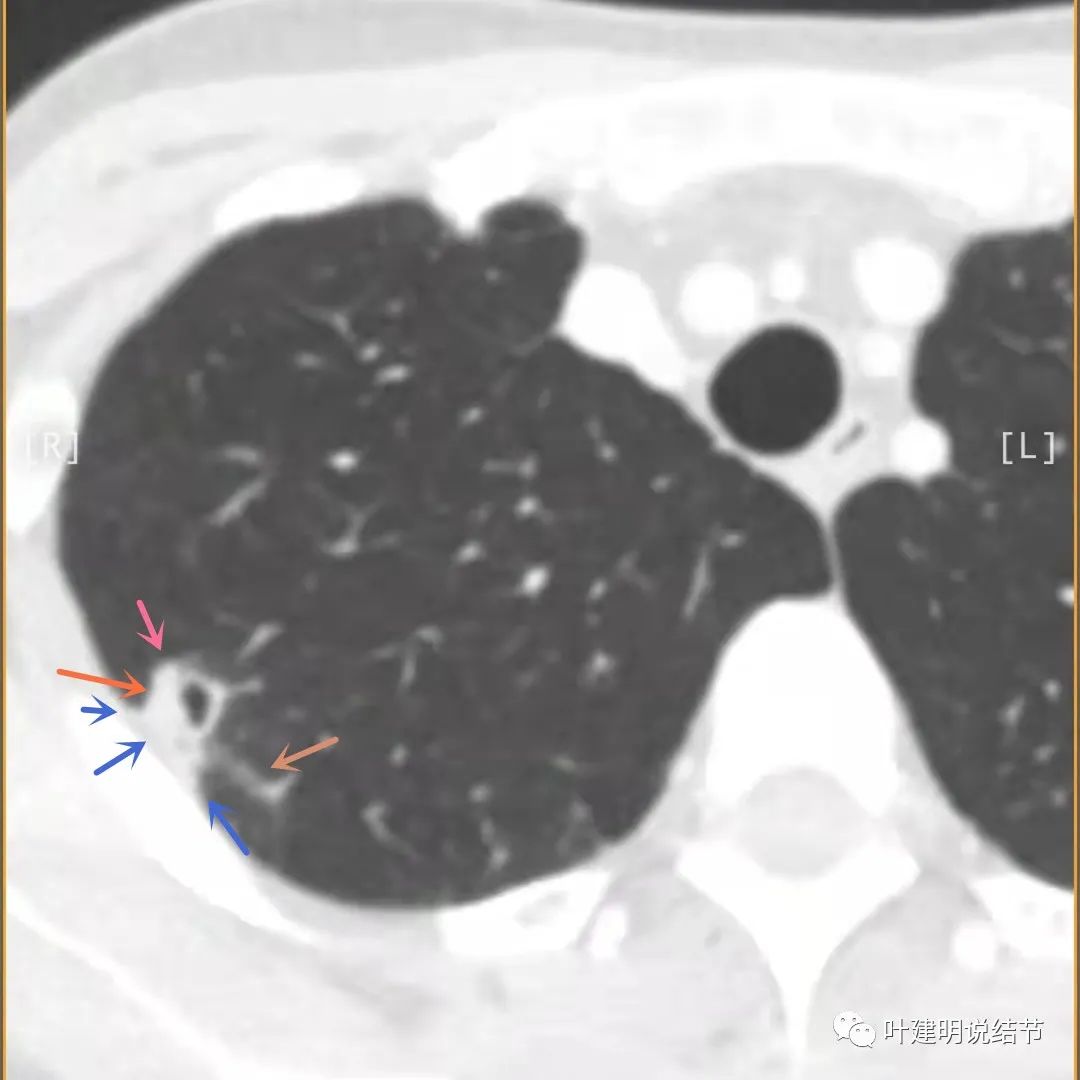

邻近胸膜明显增厚,且广基底,主病灶前方有小片磨玻璃影

主病灶与胸膜间基本相连,模糊清(蓝色箭头),主病灶壁厚薄欠均,边上有高密度条索状(桔色箭头)

主病灶不见了的层面,仍有边上高密度条索状的影像,邻近胸膜仍有异常(蓝色箭头)

影像初印象:右上病灶散在,不致密,密度偏高,磨玻璃影不是平时典型恶性的磨玻璃瘤肺边界清楚或含毛刺征的征象,更符合炎性病变,且邻近胸膜广基的异常增厚。